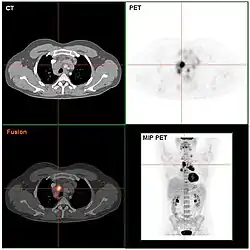

Das Ziel der folgenden klinischen Stadienbestimmung (klinisches Staging) ist es, alle Manifestationen zu erfassen und die Ausbreitung der Krankheit zu bestimmen. Das geschieht anhand der Befunde von Anamnese, Untersuchung, Laborwerten, Biopsien des Knochenmarks mit feingeweblicher Beurteilung sowie bildgebender Verfahren. Dazu gehören Röntgenbilder des Thorax in zwei Ebenen, Thorax-Computertomografie (CT), Sonografie (Ultraschall) und CT des Abdomens und eine Knochenmarkspunktion. Anstelle des CT kann bei bestimmten Patientengruppen mit Morbus Hodgkin auch die Magnetresonanztomographie (MRT) zum Einsatz kommen. Die Positronen-Emissions-Tomografie (PET) wird im Staging des Morbus Hodgkin zunehmend dann zusätzlich zur CT oder MRT eingesetzt, wenn die anderen vorgenannten bildgebenden Verfahren keinen ausreichend sicheren Aufschluss über einen Rückgang der Erkrankung unter Behandlung bieten. Ziel der PET-Untersuchungen soll sein, die Therapie noch besser nach der Erkrankungsaktivität zu steuern.